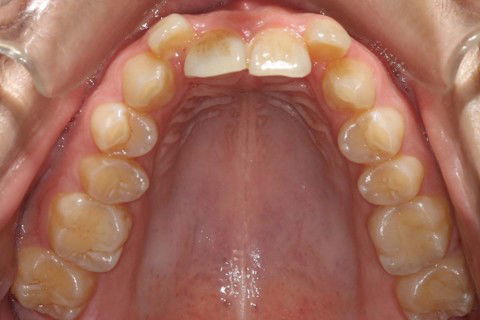

Inicial Ocl. Sup.

Inicial Ocl. Inf.

Final Ocl. Sup

Final Ocl. Inf